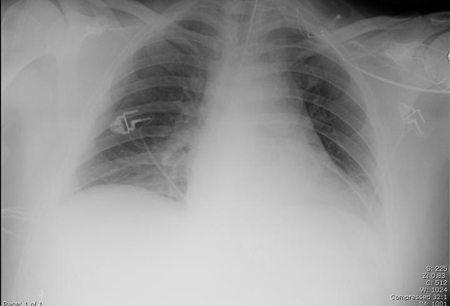

A. Portable upright chest x-ray before aspiration; B. Chest x-ray 1 hour after aspiration, showing bilateral diffuse alveolar infiltrates, worse at the bases on the right side

From the personal collection of Dr S. Murgu and Dr H. Colt, University of California at Irvine Medical Center